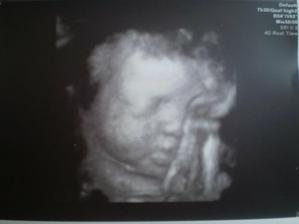

6.KO. 24.2. vše je jak má být, za dva týdny jdeme na testy na cukrovku a 4.3. jdeme na 4D ultrazvuk - už se nemůžeme dočkat

4.3. 4D UTZ bylo to super, miminko se krásně hýbalo, vypadá to, že se má u mě v bříšku dobře, doktorka nám natočila video na CD, takže máme krásnou památku